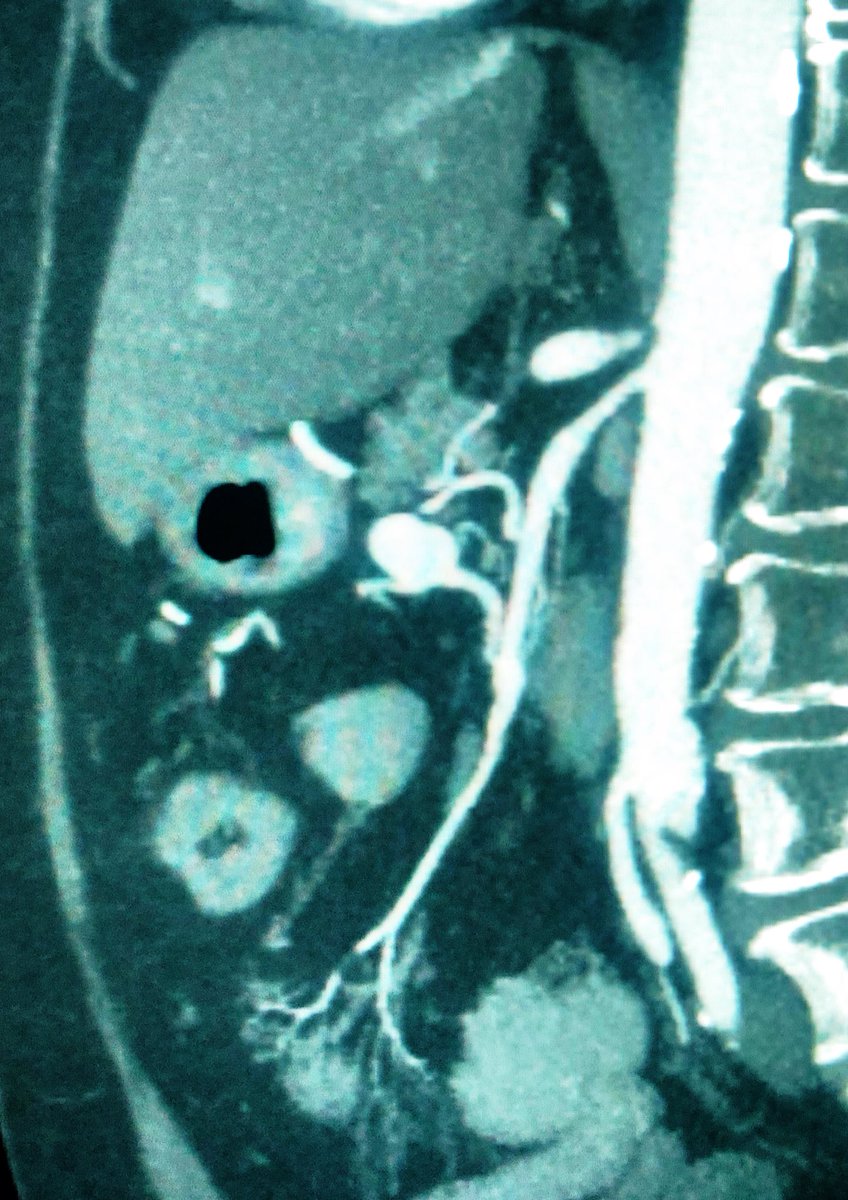

40 yo M severe L flank pain, hypotensive, admit to ICU, CT shows hemorrhage from large renal AML. Angio of torturous AML arteries, subselective run w/active🩸patient stabilized post embo, home several days later #iRad #MedTwitter #FOAMrad #PatientCare @SIR_ECS @SIRRFS @DHidlayVIR